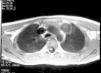

En la exploración física destacaba talla 143cm (+2,0 DE5); peso de 32,3kg (+0,2 DE5), botón mamario bilateral y estadio de Tanner8 A2P3G3-4 con volumen testicular de 4-5 cc. Con orientación diagnóstica inicial de pubertad precoz periférica, la edad ósea muestra un retraso de 2 años; en la analítica sanguínea destacan α-fetoproteína de 15,7μg/l (normal, < 15), sulfato de dehidroepiandrosterona < 0,78μmol/l (normal < 4,7), testosterona < 26 ng/dl (rango prepuberal) y β-coriogonadotropina 6,8 U/l (normal, < 0,8). El aumento de los valores de β-coriogonadotropina hace sospechar la existencia de carcinoma embrionario que se confirma mediante TC torácica, demostrándose una masa mediastínica de 2×2cm, sin otros hallazgos en el estudio de extensión, con indicación quirúrgica (fig. 2). Se realiza la resección de la masa sin incidencias, con anatomía patológica de teratoma maduro.

Ante el trastorno generalizado del desarrollo y el diagnóstico de tumor mediastínico de células germinales, se solicita cariotipo en sangre periférica, indicativo de SK (48, XXYY).

Los tumores mediastínicos de células están descritos con un riesgo entre 50 y 66 veces superior en los SK que en la población general13,14. Como fisiopatología se ha descrito un trastorno de la migración de las células germinales durante la embriogénesis; son de indicación quirúrgica y, debido a su riesgo de recidiva y asociación a otros procesos malignos, debe realizarse un seguimiento estricto15. El diagnóstico de estos tumores se realiza por efectos locales de extensión de la masa o por aparición de clínica por hipersecreción hormonal, ya que los testículos de los SK en la edad prepuberal son capaces de producir niveles de testosterona altos para inducir caracteres sexuales periféricos si son estimulados por niveles altos de β-coriogonadotropina16.